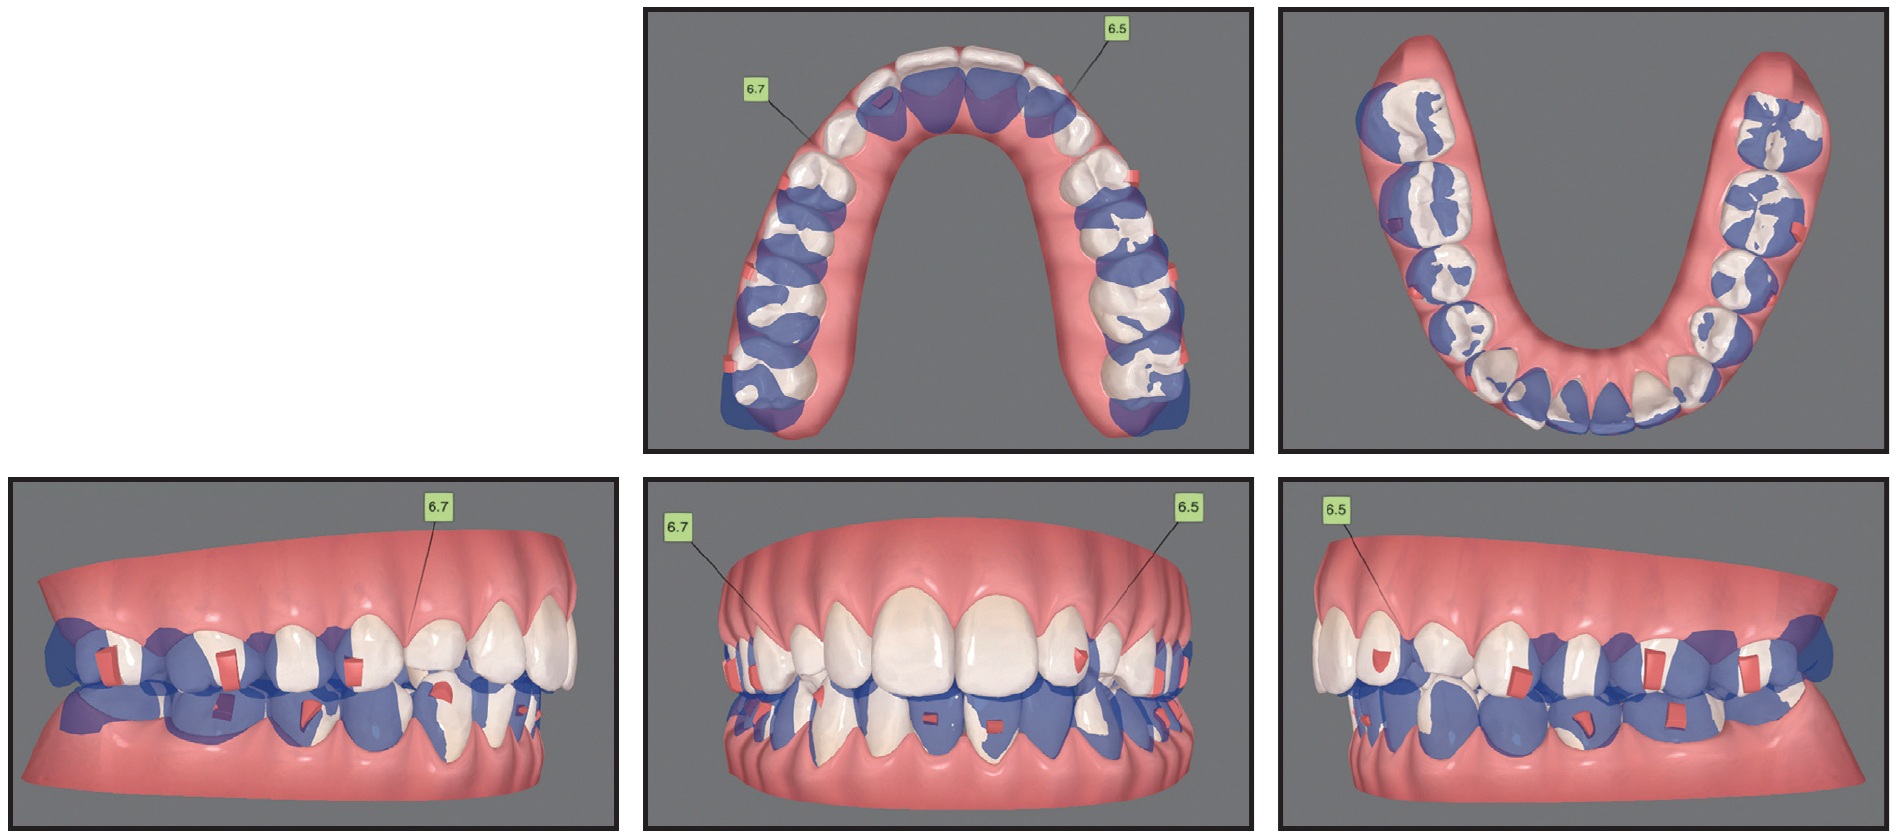

Considering the patient’s age and the locations of the impacted canines,14 the best treatment option was determined to be surgical exposure followed by orthodontic traction to bring the teeth into the arch. Invisalign clear aligners were selected to meet the patient’s preference for esthetic treatment. Additional objectives were to align the teeth and correct the Class II relationship and midline deviation. Sequential distalization would be performed in the maxillary arch (3mm on the right side and 4mm on the left), and Class II elastics would be used to prepare space for the canine and correct the Class II relationship (Fig. 2).

Fig. 2 Case 1. ClinCheck* superimposition of initial (white) and planned (purple) tooth positions for correction of Class II relationships using sequential distalization and Class II elastics.

After three stages of treatment with 118 sets of aligners, changed weekly, the canines had partially erupted, and the first refinement stage began. Twenty-six sets of aligners, changed every week, were used for this phase. Esthetic buttons were bonded to the labial sides of the impacted canines, and traction continued with elastics (3⁄16", 3.5oz) worn from the upper canines to the lower canines and first premolars and from the upper canines to the second molars (Fig. 4A). Vertical rectangular attachments were added to the lingual surfaces of the canines to correct their rotations during extrusion (Fig. 4B).

Fig. 4 Case 1. A. Application of vertical force using elastics attached from impacted canines to lower canines and first premolars, and from upper canines to second molars (continued in next image).

Fig. 4 (cont.) Case 1. B. ClinCheck plan of first refinement stage, showing use of lingual attachments on canines to improve aligner retention during extrusion and rotation.

In the final refinement phase, involving 34 sets of aligners, changed weekly, bilateral vertical cross-elastics (1⁄8", 4.5oz) were used to apply a counterclockwise moment and improve the torque of the canines while they were extruded into the arch (Fig. 5).

Fig. 5 Case 1. ClinCheck plan of final refinement stage, with vertical cross-elastics attached from lingual sides of canines to buccal sides of lower premolars to apply lingual root torque.